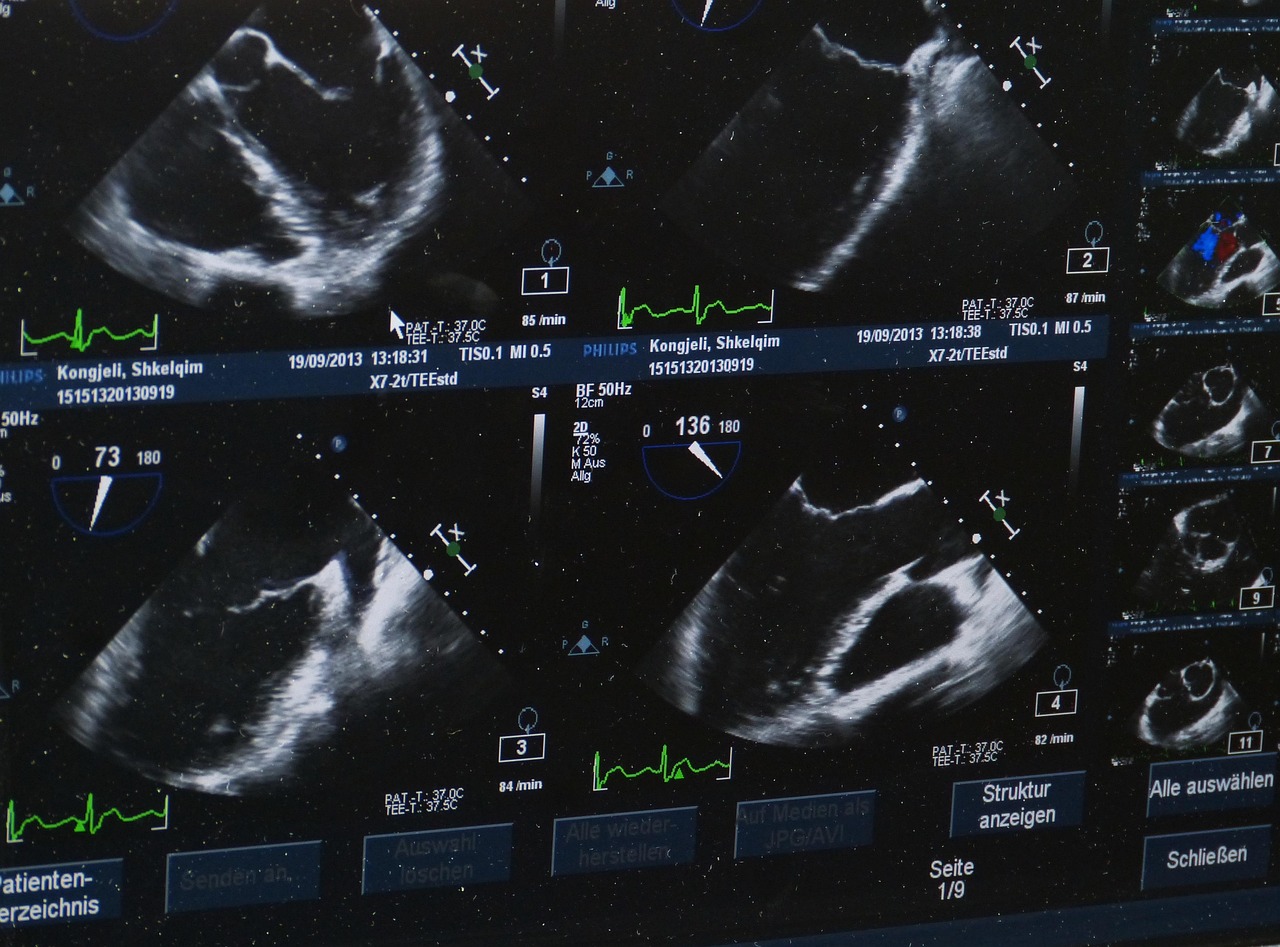

Ultraschall (Sonografie)

Bildgebende Untersuchung innerer Organe mittels Schallwellen für allgemeinmedizinische Fragestellungen - schmerzfrei und ohne Strahlenbelastung.

- Ultraschalluntersuchung nach Bedarf: Bauchorgane (Leber, Gallenblase, Nieren, Milz, Harnblase) und/oder Schilddrüse

- Dokumentation der Befunde mit Bildern